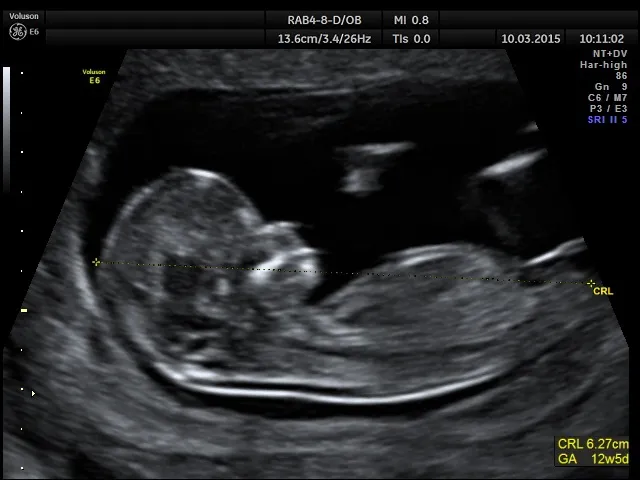

Pomiar CRL (długość ciemieniowo-siedzeniowa) złoty standard w określaniu terminu porodu

Kluczowym pomiarem podczas badania USG w pierwszym trymestrze jest długość ciemieniowo-siedzeniowa płodu, czyli CRL (Crown-Rump Length). Jest to odległość od czubka głowy do pośladków maluszka. Dlaczego ten pomiar jest tak precyzyjny? Ponieważ na wczesnym etapie ciąży wszystkie płody rozwijają się w bardzo podobnym tempie. Oznacza to, że płód w 8. tygodniu ciąży będzie miał niemal identyczną długość CRL u każdej kobiety. Dzięki temu, mierząc CRL, możemy z dokładnością do kilku dni określić wiek ciąży, co jest niezwykle cenne, zwłaszcza gdy data ostatniej miesiączki jest niepewna.

To bardzo częste pytanie i ważna kwestia. Jeśli wiek ciąży wyliczony na podstawie daty ostatniej miesiączki (OM) znacząco różni się od wieku określonego podczas badania USG w pierwszym trymestrze zazwyczaj mówimy o różnicy większej niż 5-7 dni to za wiążącą uznajemy datę z badania USG. Dlaczego? Ponieważ, jak już wspomniałam, pomiar CRL na wczesnym etapie jest niezwykle precyzyjny i odzwierciedla faktyczny wiek płodu, niezależnie od ewentualnych nieregularności cyklu czy pomyłek w zapamiętaniu daty OM. To właśnie ta data będzie podstawą do dalszego prowadzenia ciąży, planowania badań i oceny rozwoju maluszka.